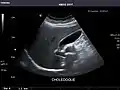

Detecting stones

Ultrasound imaging is useful for detecting stones, for example kidney stones or gallstones, because they create a clearly visible ultrasound shadow behind the stone.

Gallbladder: No stones, wall thickening, or pericholecystic fluid.